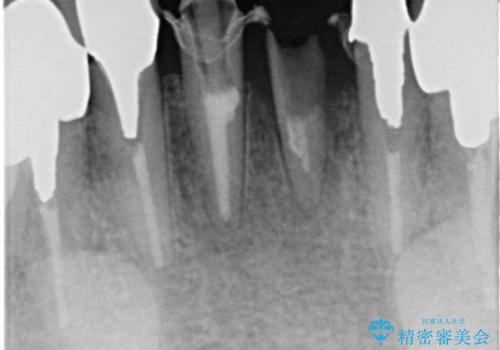

- 下の前歯のかぶせ物がが一つとれてしまい、他院で仮歯を装着されてから来院されました。

仮歯をはずし確認すると、一本の歯が土台ごとはずれて根だけになってしまって、保存が難しい状態でした。

抜歯後にブリッジを装着する計画としました。